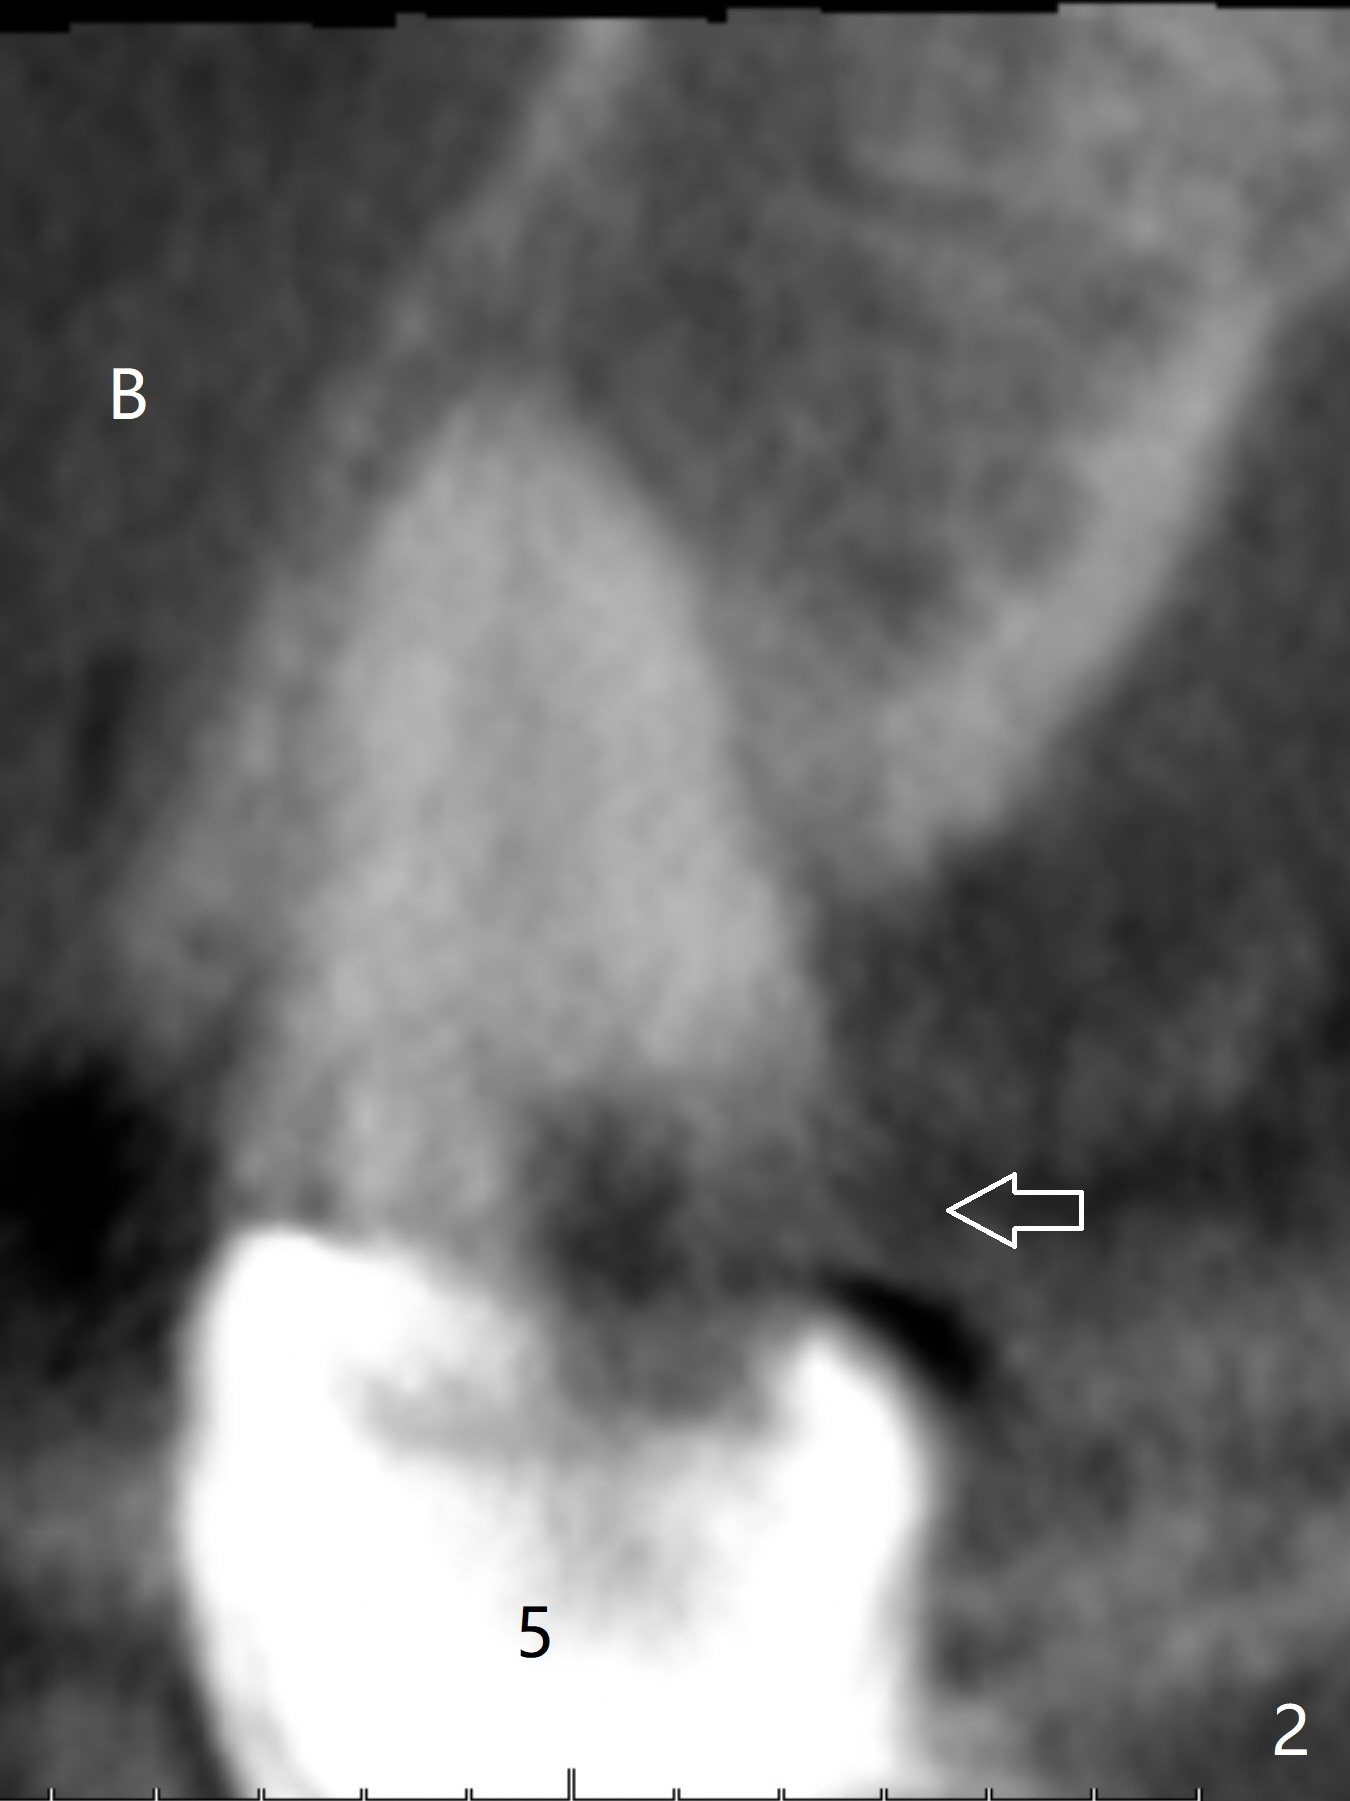

A 43-year-old woman has a failing upper right bridge (Fig.1: #2-5). While the abutment at #5 has apparently palatal open margin (Fig.2,3) and that at #4 has severe palatal bone loss (Fig.4 arrow), that at #2 has the poorest prognosis (Fig.6,7). Panoramic X-ray or PAs will be taken because of CBCT cone cut when the patient returns for #30 and 31 post-implant follow-up. Alginate impression will be taken for the upper right quadrant for provisional. The bridge will be sectioned between #3 and 5 (Fig.1 red lines) to determine salvageability of the abutments at # 4 and 5. If the latter are ok, the abutment at #2 will be extracted (expected to be loose) and implants will be placed at #2 and 3. If #4 is bad while #5 is ok, the former will be extracted and implants will be placed at #2 and 4 with a bridge. If #5 is bad while #4 is ok, implants will be placed at #2, 3 and 5.